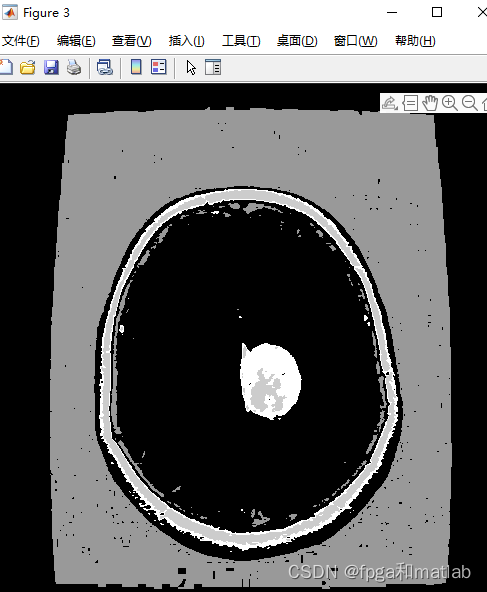

三、测试结果

通过matlab2021a仿真结果如下: